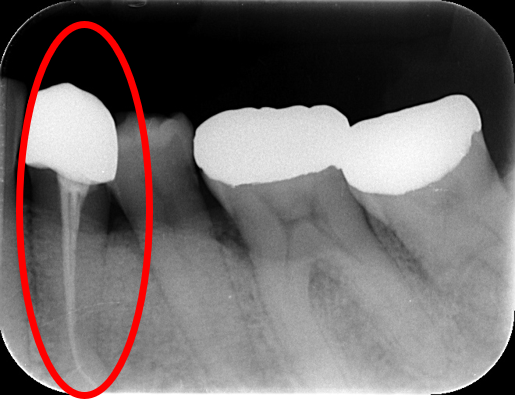

• レントゲン撮影で歯の神経に病気がみられる

7. レントゲン写真で状態を確認する

6. レントゲン写真で状態を確認する